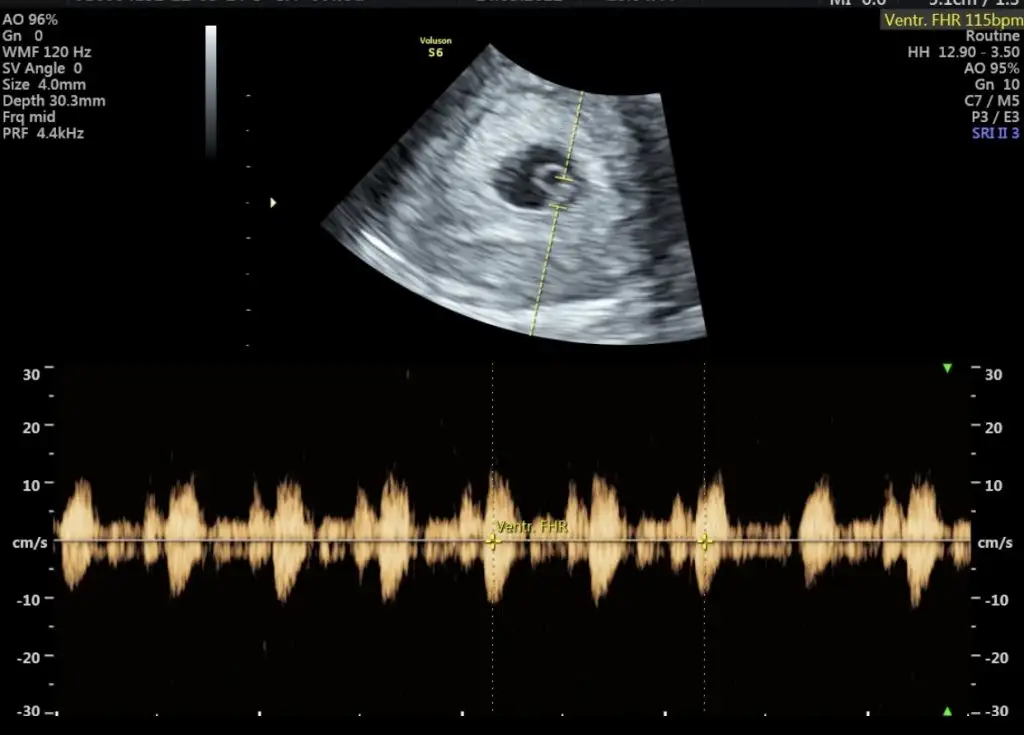

paşa mı sankiMerhaba 6+4 vajinal ultrason görüntüsüne yorum yaparmısınız çok merak ediyorummEki Görüntüle 3069814